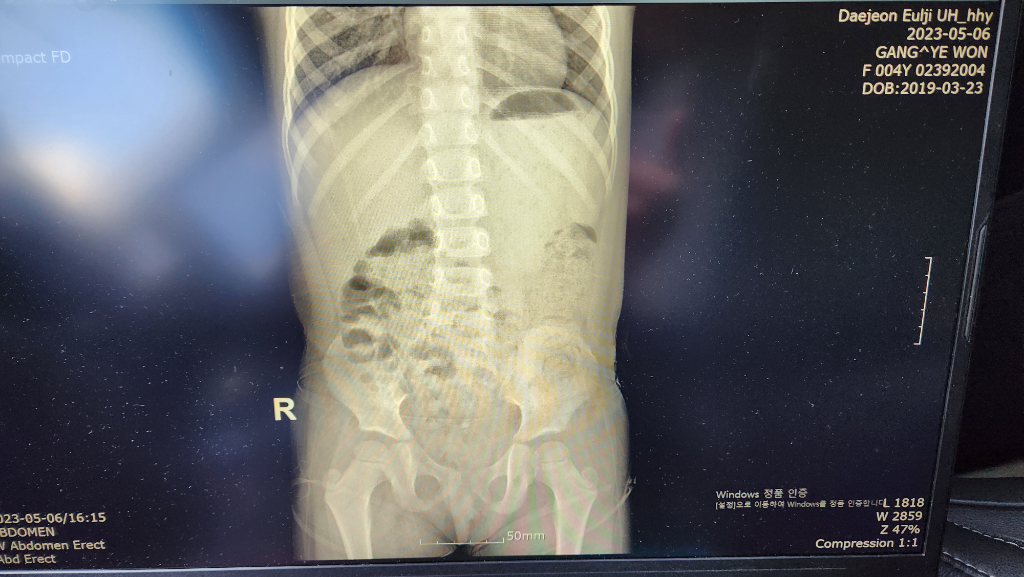

다녀와서 검색해보니 비장비대의 이유들은 무서운 이야기 뿐이더라구요, 걱정되는 마음에 응급실갔을 때(두번째 사진 23년5월, 세번째 사진 23년 11월) 엑스레이 사진을 받아왔는데 저기에도 실루엣은 보인다고 하셨습니다.

23년 5월

• 2번 째 사진

• 엑스레이 검사에서는 비장을 자세하게 관찰할 수 없습니다. 올리신 엑스레이 사진을 통해서 구체적으로 비장에 문제가 있는지 판단할 수는 없으며 정밀 검사를 하겠다면 초음파나 CT 등 검사가 필요하겠습니다. 다만, 아이에게 관련 증상이 없고 혈액 검사에서도 이상이 없는 상황에서 정밀 검사가 꼭 필요한지는 애매하며 경과를 지켜보는 것도 가능하겠습니다.